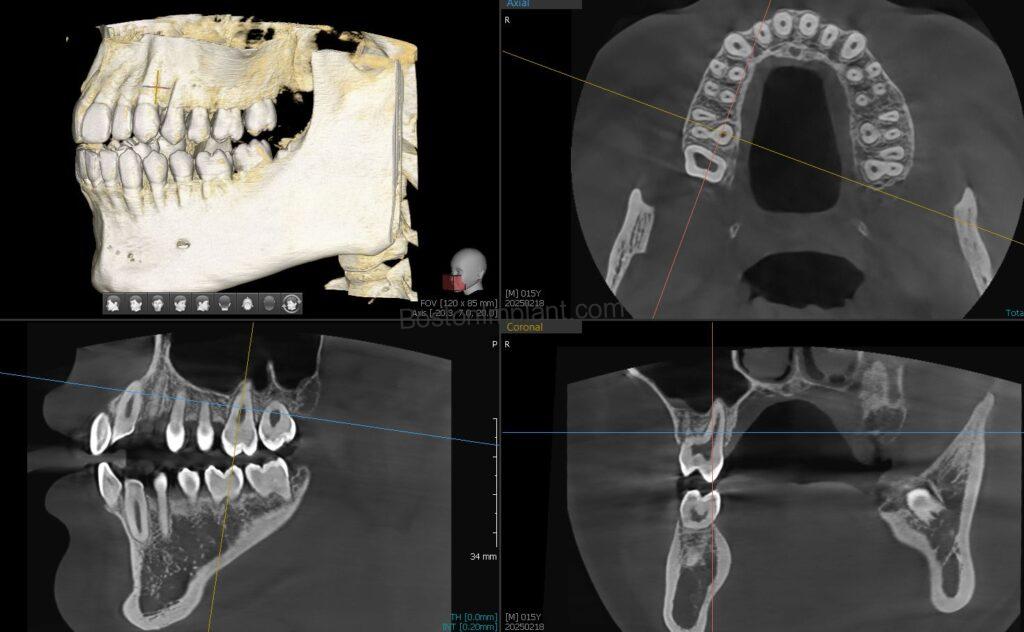

1. Planning Dental Implants: By analyzing bone shape in a three-dimensional view, we can find the optimal position and angle for dental implants. After planning, we create a surgical guide to accurately transfer the plan to the actual surgery. (Please check out our information on dental implant surgical guides!)

6. Orthodontics (Invisalign, Clear Aligners, Teeth Straightening): This is a newer application for CBCT in dentistry, but Invisalign and clear aligner patients can greatly benefit. In orthodontics, teeth (specifically their roots) move within the bone. Traditionally, we estimated root shapes based on the visible crown. Now, with 3D root and bone images from CBCT, we eliminate guesswork. This allows for more accurate simulation of root movements, ensuring the best possible outcome for your teeth straightening journey.